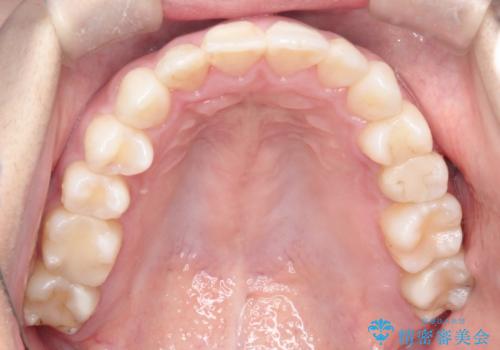

- 前歯の凸凹を主訴に来院されました。

非抜歯の範囲でできるだけ前歯を下げることを希望されたため、IPRと臼歯部の遠心移動を行い治療を行いました。当初はインビザラインで治療を行っておりましたが、使用時間を十分に確保できないことで途中からワイヤーを使用しております。

インビザラインは使用時間が不足し治療計画に支障が出る場合、ワイヤーを使用せざる得ない場合があります。(追加の治療費が必要)